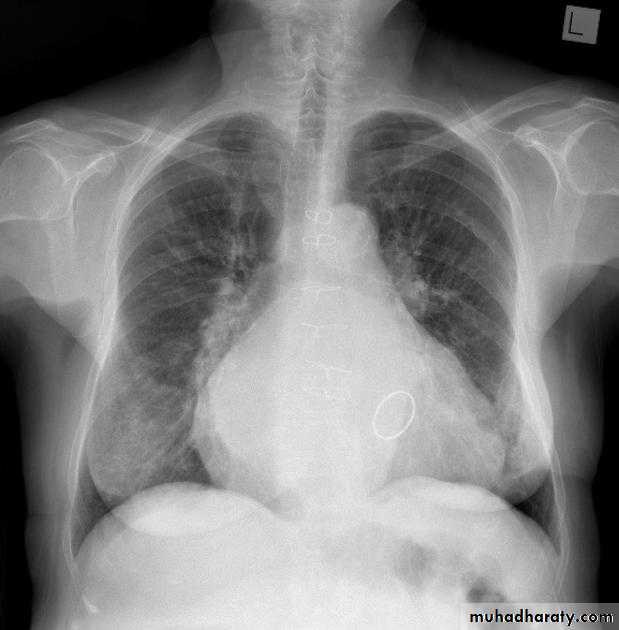

What is the main difference between 2 films ??? What is the shape of each one ??? A. B.

Emphysema

47.Emphyzema